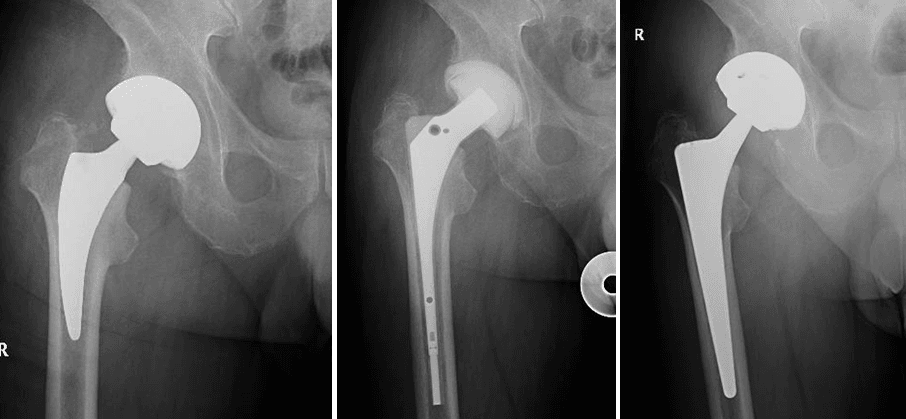

Una infezione può essere inoltre classificata sulla base del criterio temporale in acuta/precoce o ritardata/cronica. Si definisce una infezione acuta/precoce quando essa si verifica entro le 4 settimane dall’intervento di impianto protesico o dalla comparsa dei segni indicativi di infezione; in questo caso è possibile procedere con un intervento chirurgico chiamato DAIR (Debridement Antibiotic therapy Irrigation implant Retention). Oltre le 4 settimane dall’impianto protesico o dalla comparsa clinica di infezione ci troviamo di fronte ad una infezione ritardata o cronica/tardiva; in tal caso la scelta di trattamento ricadrà su un approccio chirurgico più invasivo di revisione protesica one-stage o two-stage. La scelta tra i due approcci verrà effettuata sulla base di molteplici criteri: microbiologici e clinici, relativi alla situazione infettiva attuale e alle caratteristiche generali del paziente, prendendo in considerazione diversi parametri, tra cui età, situazione dei tessuti molli, presenza di eventuali difetti ossei, condizione sistemica del paziente e comorbidità associate.

La revisione one-stage

La revisione one stage consiste nella rimozione delle componenti protesiche precedentemente impiantate, seguita da una accurata bonifica dei tessuti, prelievi intraoperatori per esami colturali e l’immediato reinserimento di una nuova protesi nello stesso intervento chirurgico. Verrà quindi avviata un

a terapia antibiotica mirata sulla base degli isolamenti microbiologici agli esami colturali.

La revisione two-stage

La revisione two stage rappresenta il gold standard per il trattamento delle infezioni periprotesiche croniche. Essa consiste nella rimozione delle componenti protesiche precedentemente impiantate, seguita da una accurata bonifica dei tessuti, prelievi intraoperatori per esami colturali e inserimento di uno spaziatore antibiotato, a cui verrà associata una terapia antibiotica mirata sulla base degli isolamenti microbiologici agli esami colturali. Costituisce l’opzione più valida e sicura nei casi di infezione peri-protesica difficile da trattare sia per motivi legati al germe patogeno resistente o difficile da isolare, sia per difficoltà dal punto di vista ricostruttivo a causa di importante perdita ossea e/o mio-cutanea. Il doppio tempo chirurgico rappresenta un’ottima soluzione per bonificare in maniera adeguata il sito infetto, consentendo al paziente di mantenere una buona qualità di vita, grazie allo spacer articolato che vicaria la funzione della protesi, e permettendo al chirurgo di pianificare in maniera ottimale il tempo del reimpianto.